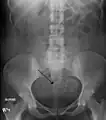

Diagnosis

Physical examination and ultrasound are sufficient for diagnosing uterine fibroids in the majority of patients. When ultrasound findings are inconclusive, magnetic resonance imaging (MRI) may be able to confirm the diagnosis of uterine fibroids in most cases. In addition, MRI can identify benign uterine fibroids with atypical imaging features and fibroids with variant growth patterns. MRI can also identify other uterine (e.g. adenomyosis, endometrial polyps, endometrial cancer) and extrauterine (e.g. benign and malignant ovarian tumors, endometriosis) disorders that may mimic the appearance of uterine fibroids and/or contribute to the patient's symptoms.[37] However, a small proportion of uterine fibroids can mimic other malignant uterine tumors (e.g. leiomyosarcoma) on all available imaging modalities (e.g. ultrasound, CT, MRI and PET-CT).[37]

Malignant tumors of the uterine wall (e.g. leiomyosarcoma) are very rare. Findings suggestive of a malignant uterine tumor rather than a benign fibroid include, fast or unexpected growth (particularly after menopause), interruption/effacement of the endometrial stripe, lymph node enlargement, invasion of adjacent organs and metastases to distant organs (e.g. lung). MRI findings suggestive of a malignancy include nodular/ill-circumscribed tumor margins, intermediate/high T2-weighted signal intensity of the solid tumor components, regions with high signal T1-weighted sequences in keeping with subacute hemorrhage, fine/wispy enhancement of the solid parts of the tumor, and restricted diffusion on diffusion-weighted imaging (DWI).[37] A biopsy is rarely performed and if performed, is rarely diagnostic. Should there be an uncertain diagnosis after ultrasounds and MRI imaging, surgery is generally indicated.[38]